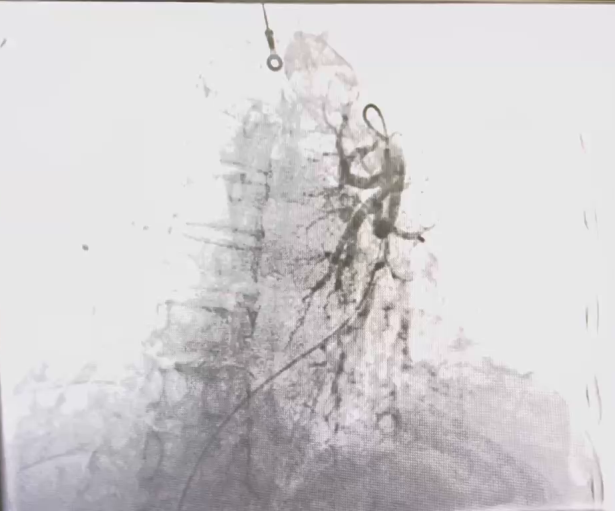

3.患者氧合指数极低,I型呼吸衰竭,持续经鼻高流量氧疗;结合患者既往病史、临床症状及辅助检查,考虑患者冠心病、全心功能衰竭,并不排除肺栓塞可能,于9月26日行冠状动脉造影术+肺动脉造影术+必要时冠状动脉内支架置入术。经过精心治疗,患者于近期好转出院。

患者行介入手术      患者造影结果